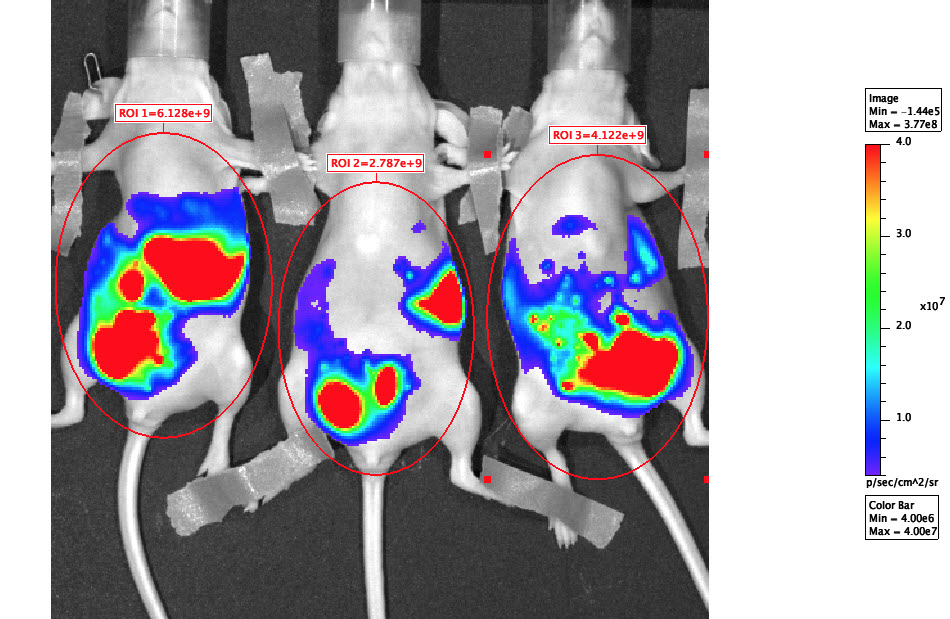

Dr. Daniela Dinulescu is utilizing an original recombined ovarian cancer cell line to inject into mice while testing two different treatments: the olaparib and the olaparib with cisplatin combination treatment. The project will ultimately demonstrate the effectiveness of the treatments as well as model the growth path of the tumor within the animal.